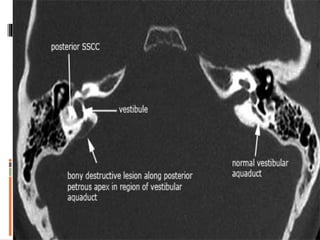

 CT scan (normal aperture 6mm but in meniere 2mm)

 MRI (rule out CP angle lesions)